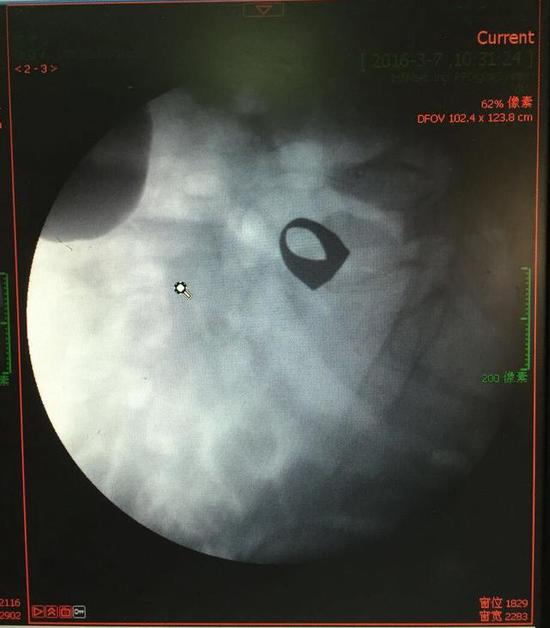

考慮到患者年齡較大,有冠心病,曾經(jīng)中過風,高血壓極高危級,遂把老人安排在帶有監(jiān)護的病房,立即給予吸氧,補液等治療。醫(yī)院立刻開啟綠色通道,醫(yī)護人員專門陪伴病人做了增強CT,腹部平片,和碘水造影,確定戒指的位置。檢查結(jié)果提示戒指位于右下腹小腸內(nèi),距回盲瓣體表投影約5cm。

在該院胃腸外科,舒曉剛教授、夏澤鋒副教授接診了張大爺,并制定下一步治療方案?紤]到患者年齡大,身體狀況不好,內(nèi)科基礎病較多,手術(shù)取戒指風險太大,花費高。在綜合考慮后,胃腸外科專家組打算用微創(chuàng)結(jié)腸鏡技術(shù)嘗試取出戒指。結(jié)腸鏡一般用于結(jié)直腸檢查,一般很難通過回盲瓣,檢查到小腸,必須要有經(jīng)驗的醫(yī)生來做。

3月9日,夏澤鋒教授細心的給病人做結(jié)腸鏡檢查,找到回盲瓣,調(diào)整結(jié)腸鏡鏡頭,快速的進入小腸。結(jié)腸鏡緩緩上行至距離回盲瓣5cm的小腸,沒有戒指。繼續(xù)上行,至20cm的地方,仍然沒有找到戒指。

“消失的金戒指” 終于排出

此時一個又一個大大的疑問出現(xiàn)在每個在場的醫(yī)護人員腦海中,戒指還在小腸里嗎?戒指在哪個位置呢?夏教授立刻聯(lián)系放射科,拍片子,發(fā)現(xiàn)戒指已經(jīng)移動了,從右側(cè)移動到了左側(cè)去了。放射科醫(yī)師建議,戒指有可能會繼續(xù)沿腸道下行,如果過了回盲瓣,就可以自行排出,免除手術(shù)痛苦。教授們采納了這個意見,立即給予促進胃腸道動力藥,枸櫞酸莫沙必利片,每日口服三次,另外配合灌腸治療,促進腸道蠕動,利于戒指排出。